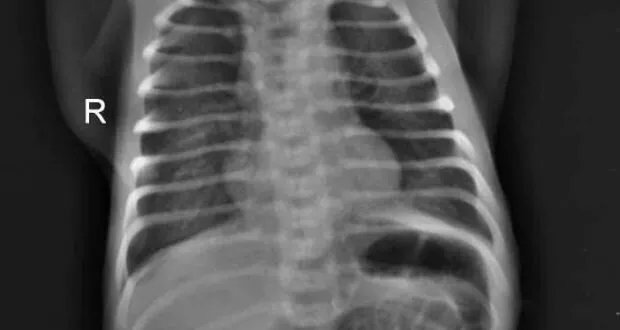

بعد ٦ ساعات، أظهرت صورة الصدر علامات داء الأغشية الهلامية، وتمت معالجته بالمراقبة السريرية والشعاعية والتمريضية الدقيقة، مع دعم بالأوكسجين عبر قنية أنفية بتركيز ١ل/د، بالإضافة إلى السوائل الوريدية والتغطية الانتانية التخبرية.

في اليوم الثالث للولادة، تدهورت حالة الطفل مع ازدياد الاعتماد على الأوكسجين وازدياد صعوبة التنفس. تم إجراء صورة صدر بوضعية الوقوف أظهرت ريح صدرية ثنائية الجانب. تم استشارة د.جوني نادر (أخصائي في جراحة الأطفال) وتقرر إجراء تفجير صدر إسعافي بالجهتين.